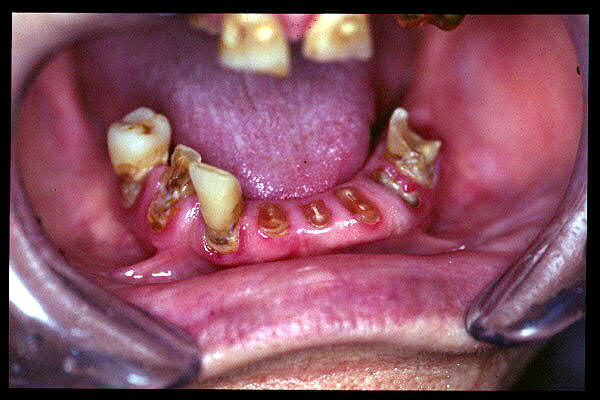

CM Desgaste por bruxismo, presencia de cálculo